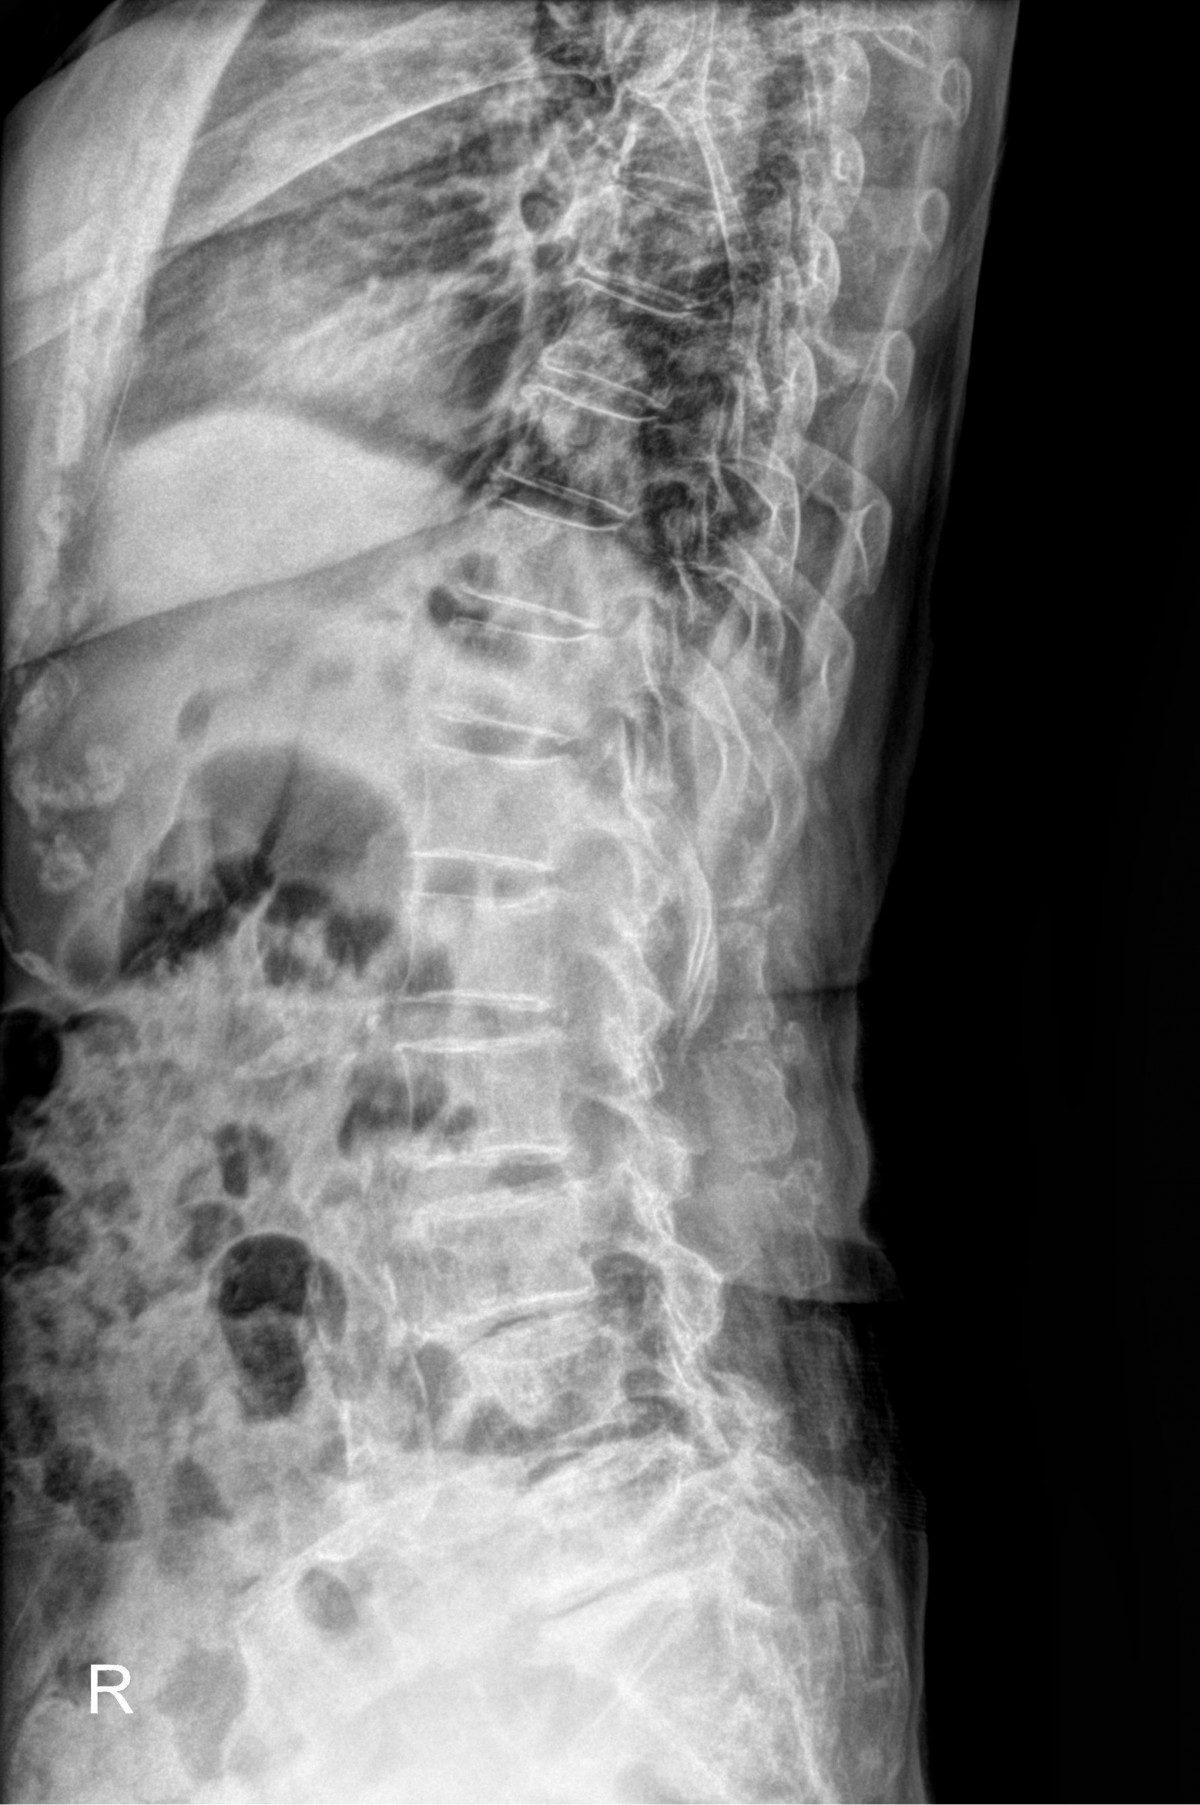

최원락원장님 허리골절 골시멘트 성형술 나공O 환자

32341c324db2d176f34ec014ac758183_1729061246_3268.jpg

32341c324db2d176f34ec014ac758183_1729061259_4473.jpg